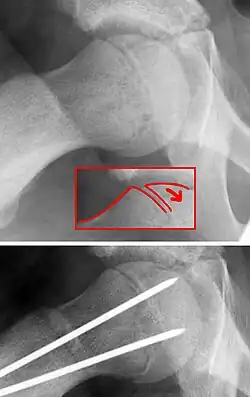

Auf einem Röntgenbild der Hüften, insbesondere einer Beckenübersichtsaufnahme, ist die Ablösung des Gelenkkopfes nicht immer gut zu sehen. Wichtig ist daher eine zusätzliche axiale Aufnahme in Lauenstein-Projektion beidseits, auf welcher die Fehlstellung der Epiphyse gut erkannt werden kann. An dieser Aufnahme wird der Abrutschwinkel bestimmt. Aus diesem Winkel ergeben sich therapeutische Konsequenzen.

Um eine mögliche Femurkopfnekrose zu vermeiden und eine spätere Belastbarkeit des betroffenen Gelenkes zu erreichen, ist die operative Fixierung notwendig. Dazu dienen bei jungen Patienten mit noch deutlichem Restwachstum Bohrdrähte, die parallel zum Schenkelhals über die Wachstumsfuge in die Epiphyse vorgeschoben werden. Bei erheblichem akuten Abrutsch muss erst der Hüftkopf durch Innenrotation und Zug reponiert werden. Bei älteren Kindern ohne wesentliches Restwachstum (Y-Fuge bereits verschlossen) werden Schrauben mit kurzem Gewinde in gleicher Richtung in den Hüftkopf eingebracht. Der Eingriff wird Epiphyseodese genannt, die Wachstumsfuge wird überbrückend stabilisiert. Nach Abschluss des Wachstums wird das Osteosynthesematerial (Drähte oder Schrauben) entfernt.